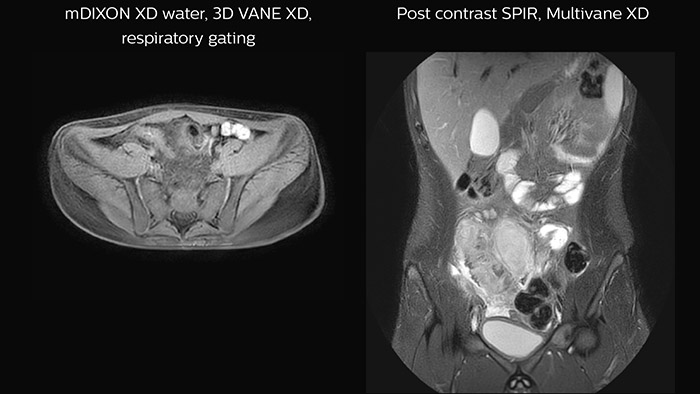

Body-oncology ExamCards for 1.5T

Examples of 3.0T neuro-oncology ExamCards (left) and 1.5T body-oncology ExamCards (right) for a selected age group. The list of sequences from the highlighted ExamCard is shown on the right. These ExamCards are part of the Philips DACH Pediatric Reference Scan Protocols